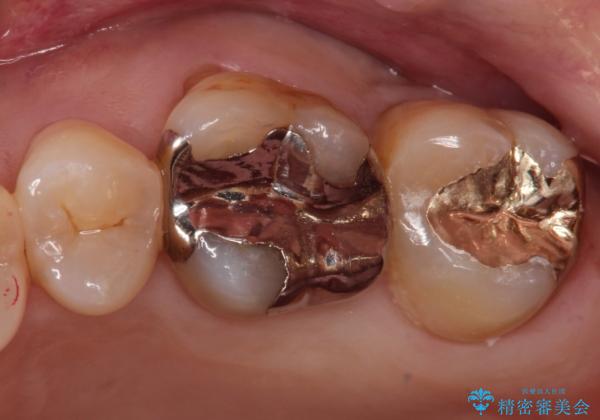

銀の詰め物が外れた。プラチナゴールドインレー

- 銀の詰め物が外れたことを主訴に来院されました。

適合の良い修復を希望されましたので、プラチナゴールドインレーにて治療を行っております。

PGA(プラチナゴールド)インレーは適合もよく、壊れるリスクも極めて少ない修復です。